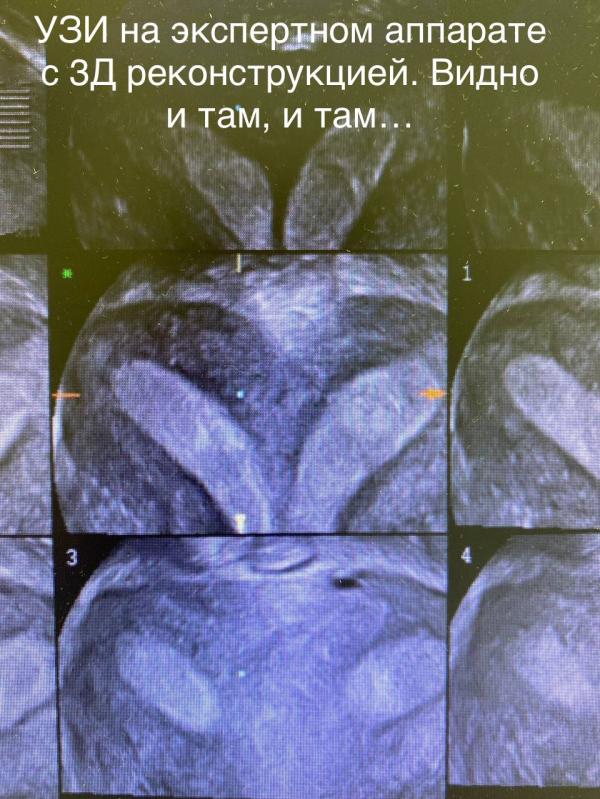

Пациентка, работает учителем в школе, ежегодно в течение 10 лет проходила проф.осмотры. Без особенностей.

Обратилась с жалобами на нарушение менструального цикла. При осмотре выявлено полное удвоение матки и шейки матки…

Женщина ведь ежегодно сдавала цитологию шейки матки. Вопрос «Из какой шейки»…? Правой или левой?🤦🏼♀️Получается, скрининг на рак брали из какой?

Я вот не понимаю, это как можно не заметить? 2 полноценные матки и...